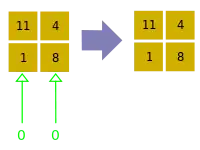

- A basic premise in back-projection is that any attenuation of the X-ray beam has occurred uniformly along the path followed from the source to the detector. Let's consider a simple tomographic slice containing just four voxels to illustrate the computational approach - see Figure 7.11. The first projection, P1 is obtained from a horizontal exposure from left to right in the figure. The back-projection of P1 involves putting the values 7 and 9 in both elements of the first and second rows, respectively. The second projection, P2 adds a 4 to the top right element, 1 to the bottom left element and 11 to the other two elements when it is back-projected. The other projections are treated in a similar fashion. Following regularisation of the data set the final image is obtained at the bottom left of the figure.